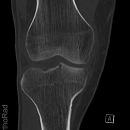

Kniegelenk